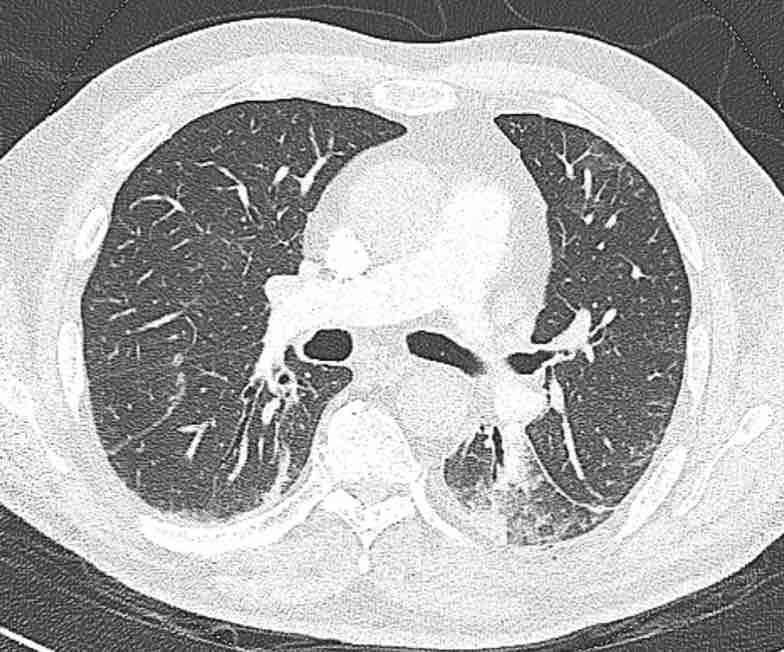

Các phân thùy phổi trên CT

Cuộn qua các hình ảnh để quan sát cách phổi được phân chia thành các phân thùy.